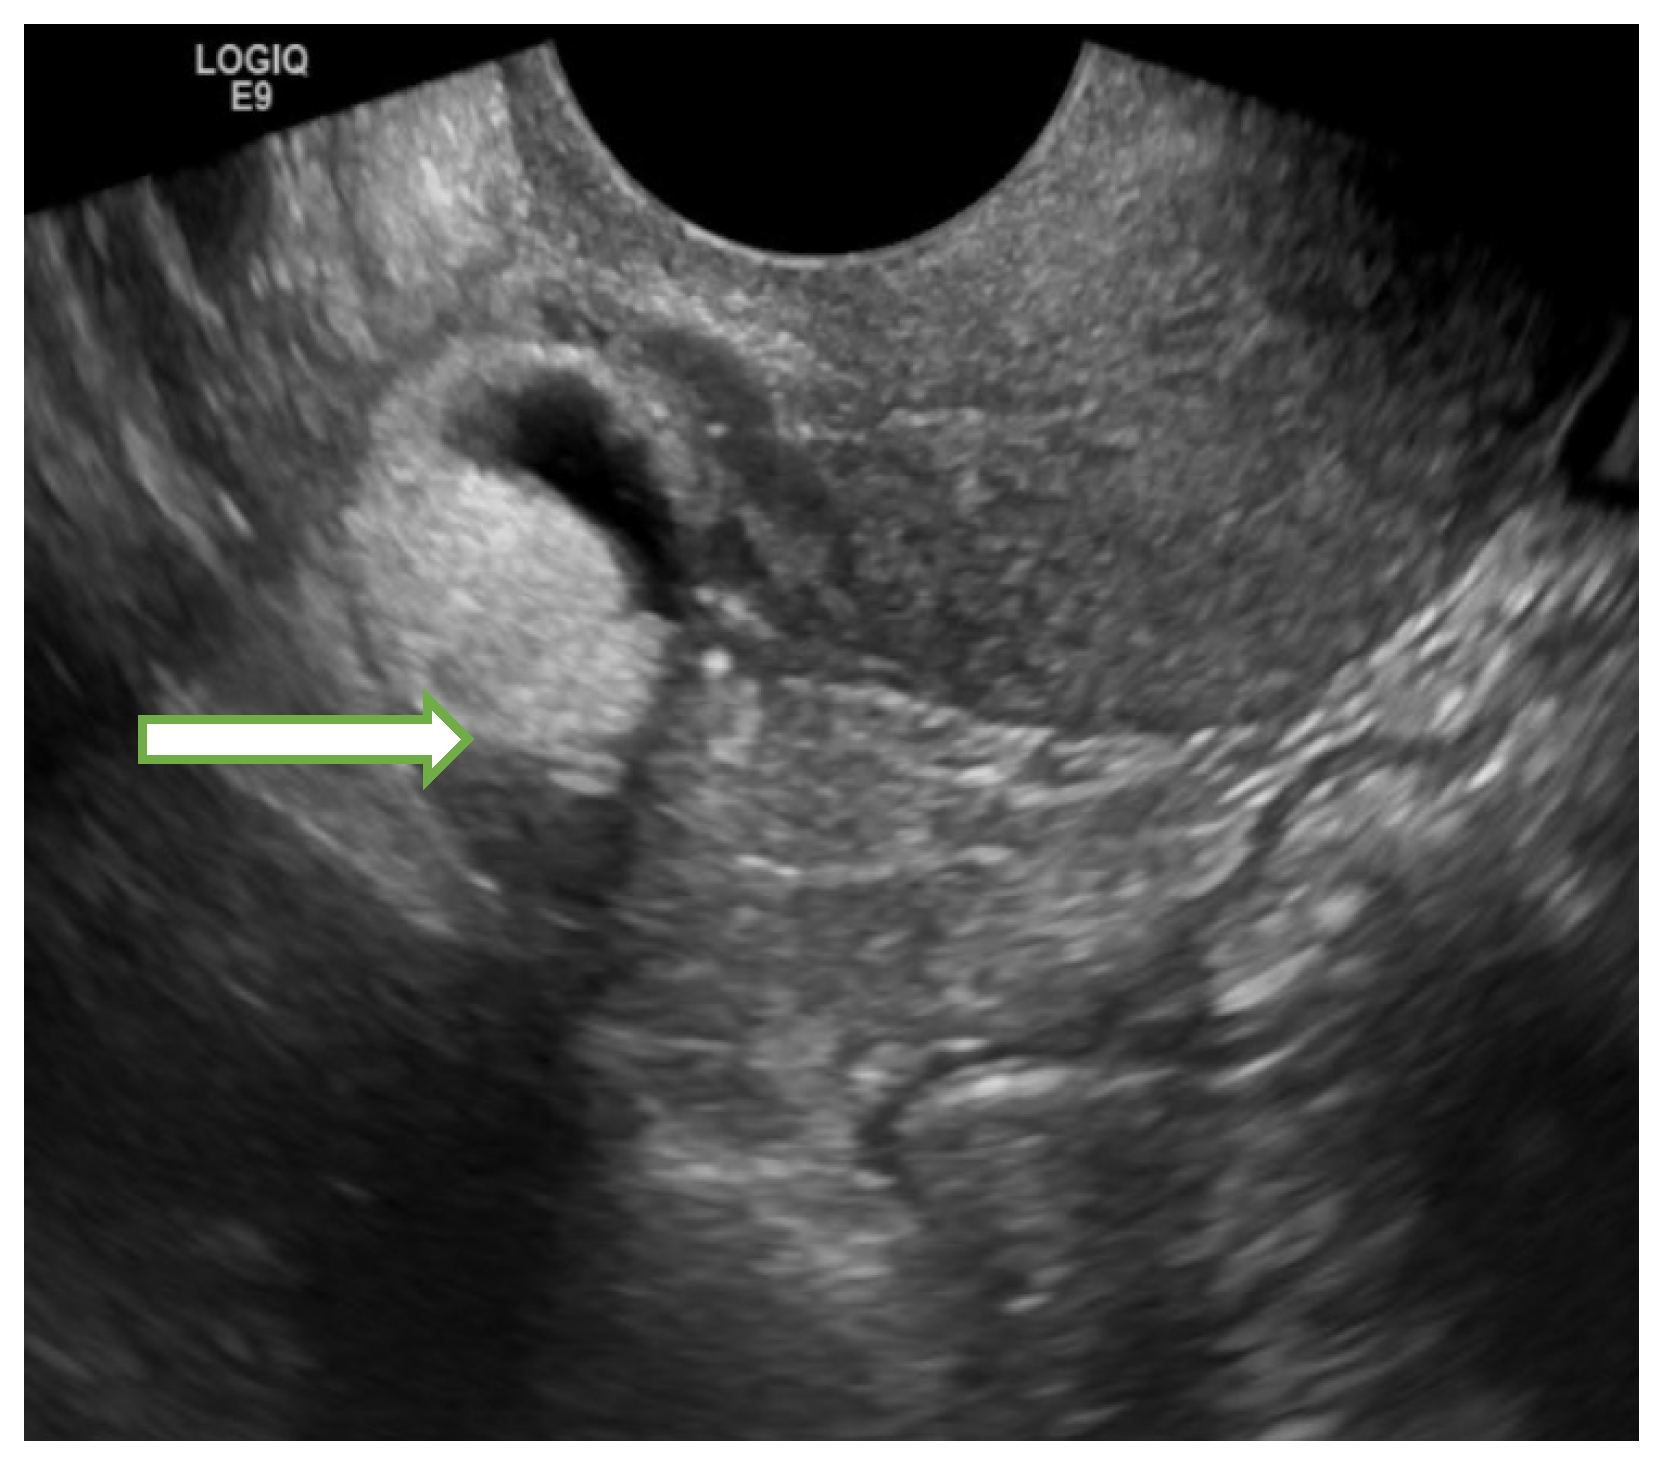

4.1. Ultrasound

- Hsiao, Y.-H.; Yang, S.-F.; Chen, Y.-H.; Chen, T.-H.; Tsai, H.-D.; Chou, M.-C.; Chou, P.-H. Updated applications of Ultrasound in Uterine Cervical Cancer. J. Cancer 2021, 12, 2181–2189. [Google Scholar] [CrossRef]